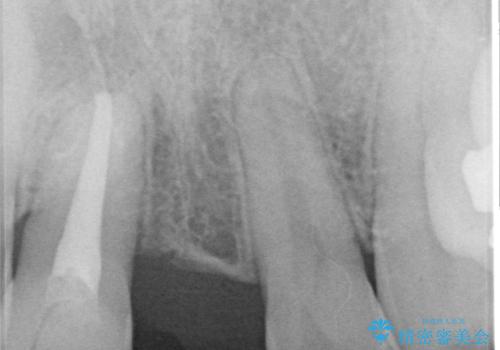

- 転倒により前歯を失ったところにインプラント治療を受けたいとのことで来院された患者様です。

転倒を機に矯正治療を行ったようで、歯列が整い、インプラントのスペースができたとのことで受診をされました。

骨量は十分にあったため、インプラント埋入後速やかに仮歯を装着して、歯肉治癒後にオールセラミッククラウンによる補綴治療を行うこととしました。